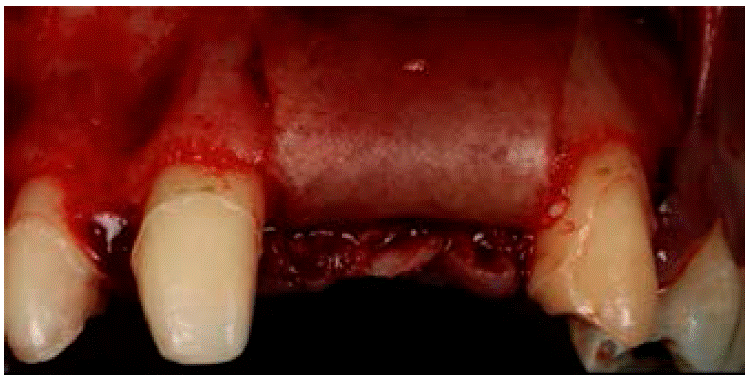

Se administró anestesia local de articaína al 4% usando agujas cortas por medio de la técnica de infiltración. Se bloqueó el nervio alveolar superior anterior y el nervio nasopalatino. Posteriormente se realizó una incisión de incisivo lateral superior derecho a canino superior izquierdo de forma trapezoidal con preservación de papilas, para lo que se empleó un mango de bisturí 3 Bard Parker y una hoja de bisturí número 15C. El desprendimiento de colgajo mucoperióstico se efectuó con una la legra Prichard (Figura 6).

Figura 6: Desprendimiento del colgajo mucoperióstico y observación del defecto óseo. (Fuente original).